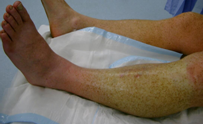

Βλάβη ασβεστυλοφυλαξίας στη δεξιά γαστροκνημία. (Ευγενική παραχώρηση Dr. V. Penopoulos).